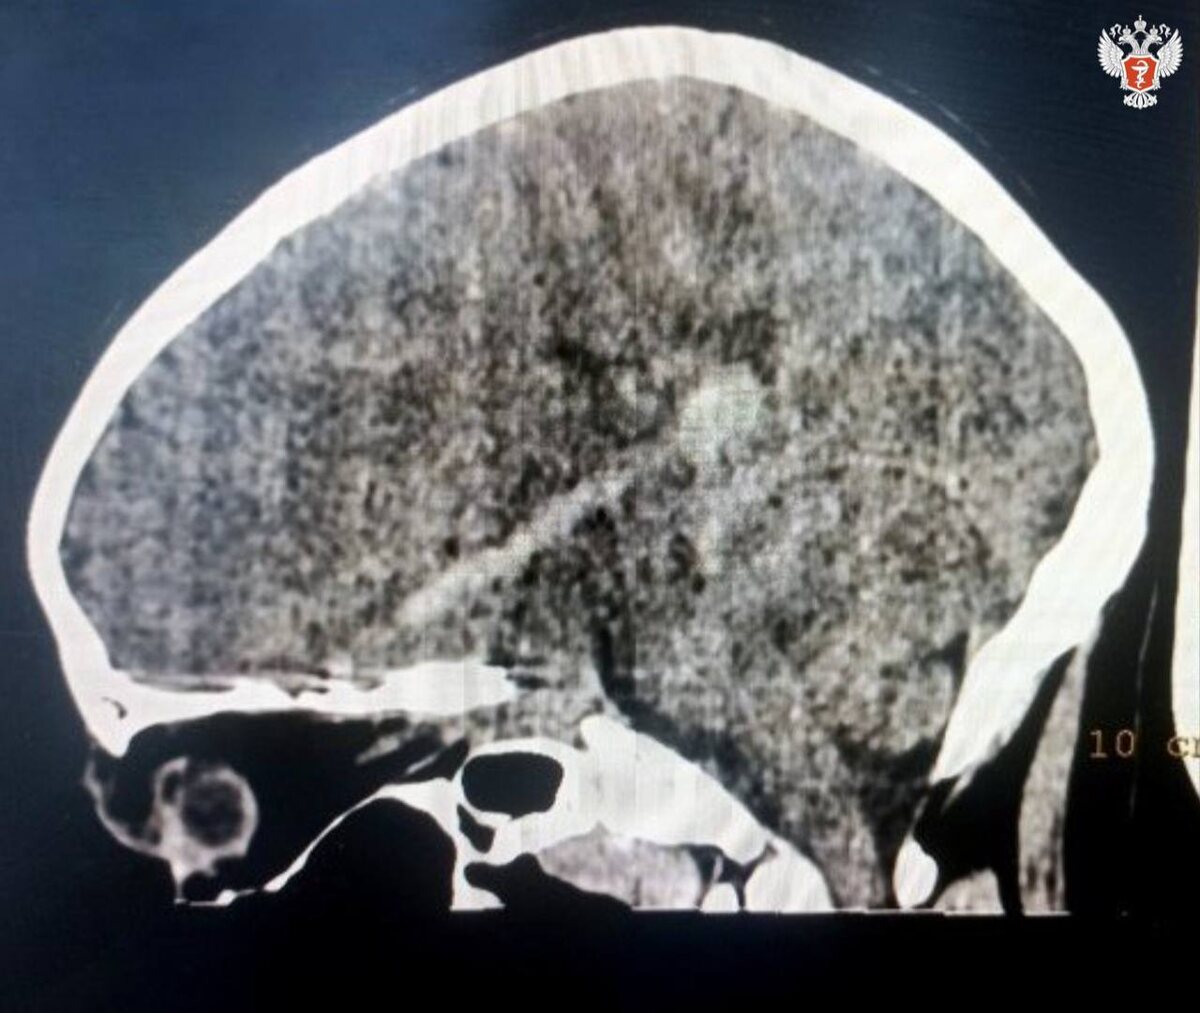

Во время уличных игр мальчик упал на шампур, который проткнул глазницу над веком и вошёл в череп.

⚠️ В тяжёлом состоянии его доставили в Котельничскую ЦРБ, откуда экстренно эвакуировали в Центр травматологии Кирова.

🧠 Диагноз:

– Открытая проникающая рана головы

– Ушиб головного мозга

– Внутримозговая гематома

– Перелом основания черепа